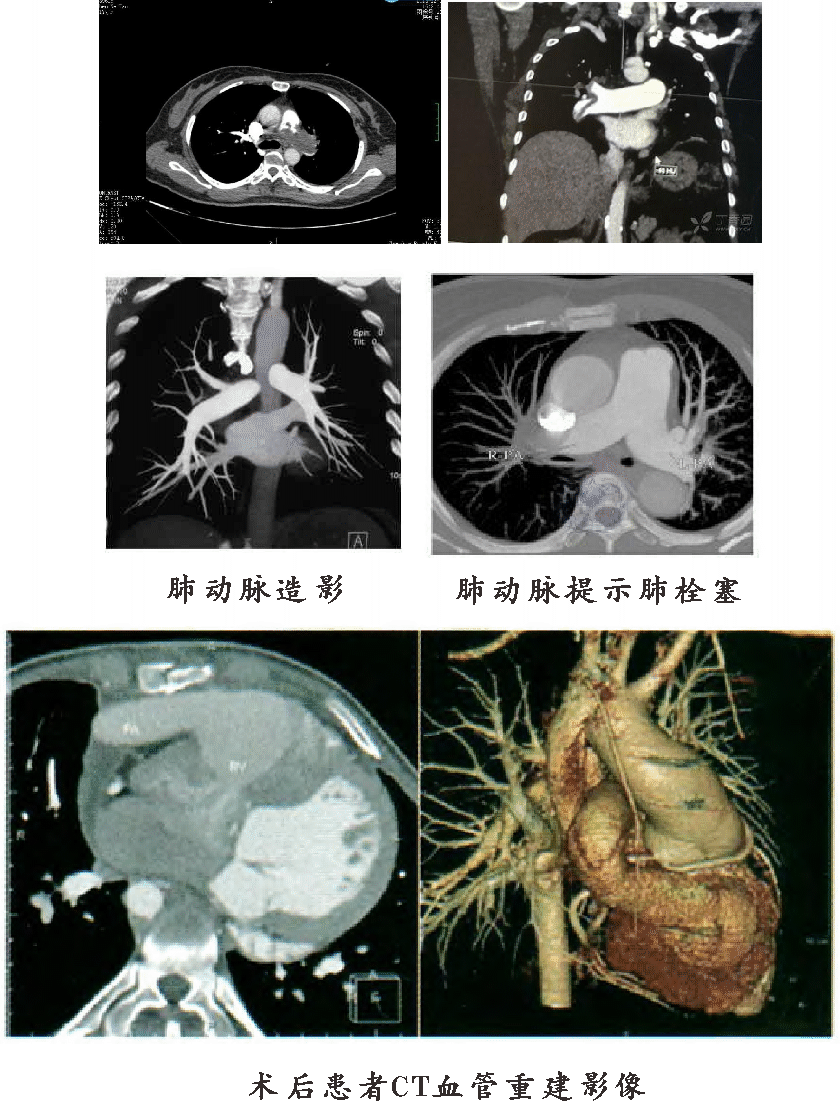

●CT肺动脉造影(CTPA)

我科引进德国先进的西门子64排128层CT, 利用其扫描速度快、薄层扫描等特点,精确追踪肺动脉最佳显影时间,清晰、直观显示肺动脉及其分支血栓的大小、面积、密度,以及与肺动脉壁关系。利用多平面重组(MPR),实现轴位、冠状位、矢状位、任意斜位显示肺动脉影像,为临床治疗方案的选择提供指导性作用,同时还可以作为术后评估。与单排CT相比,特异性、敏感性明显提高,进一步提高肺段动脉、亚段动脉栓塞的检出率,是肺动脉栓塞首选的检查方法。